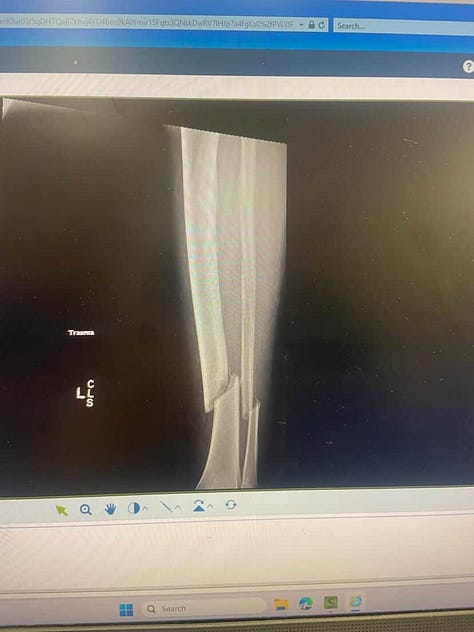

I’m writing this from my bed and current makeshift office in the weeks following a major orthopedic trauma surgery after a complete tibia and fibula fracture sustained during a rugby game.